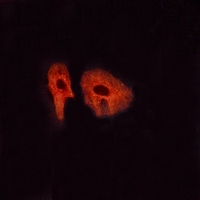

Immunofluorescent analysis of Glucagon Receptor staining in HeLa cells. Formalin-fixed cells were permeabilized with 0.1% Triton X-100 in TBS for 5-10 minutes and blocked with 3% BSA-PBS for 30 minutes at room temperature. Cells were probed with the primary antibody in 3% BSA-PBS and incubated overnight at 4 °C in a hidified chamber. Cells were washed with PBST and incubated with a AF594-conjugated secondary antibody (red) in PBS at room temperature in the dark.